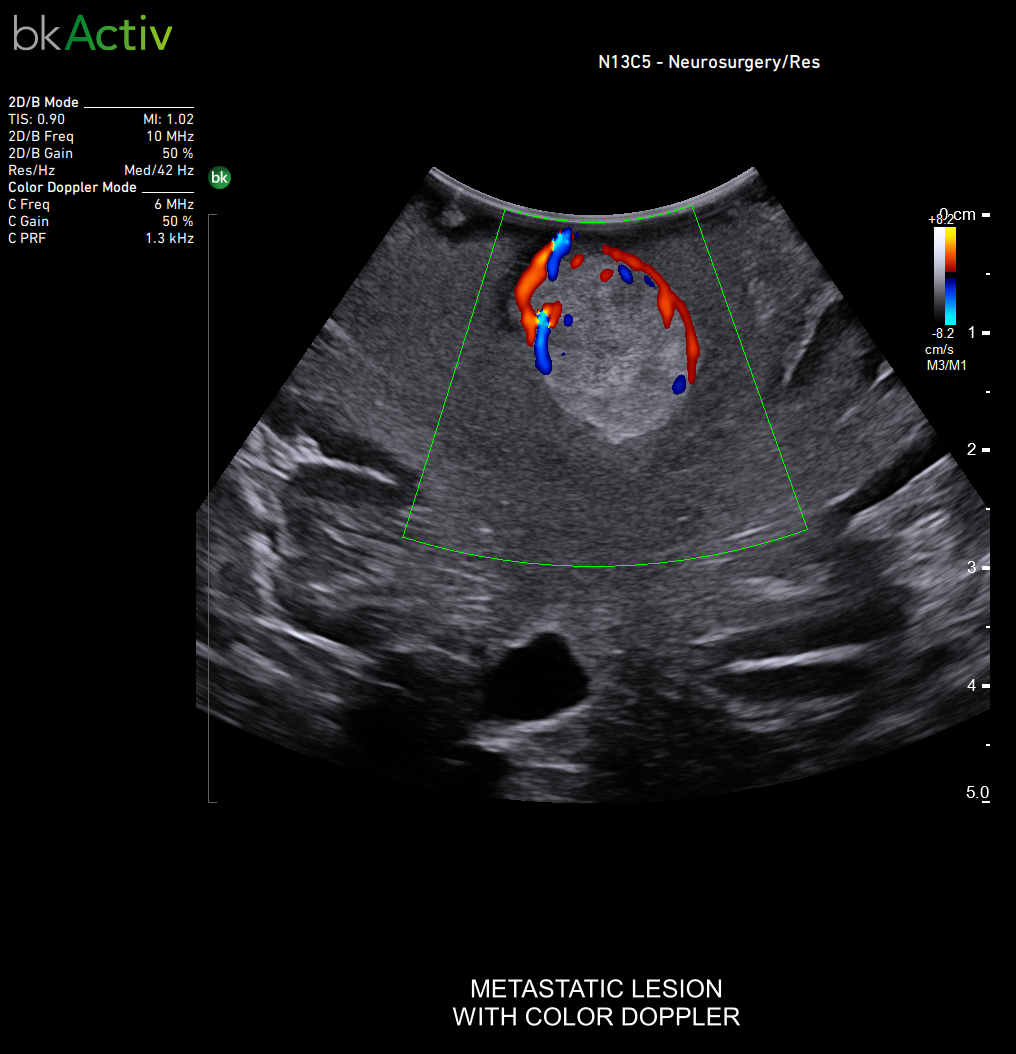

Neurosurgery and Spine

Improved algorithms that automatically allow uniform image resolution, greater details around lesion borders and at larger depths, and enhanced penetration, spatial resolution, and near field image quality.